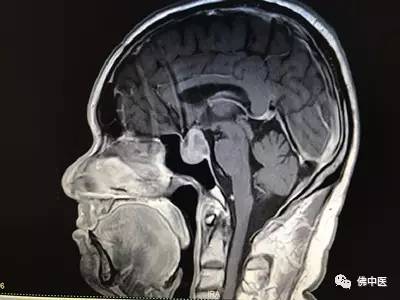

来自河源的刘先生十多年来饱受慢性顽固性头痛的困扰,近一年多来还出现了视力模糊的症状,经当地医院脑部核磁检查才惊现,原来脑部眼后方处有一个近3cm的肿瘤,正是肿瘤压迫才导致顽固性头痛和视力模糊。当地医生告诉刘先生要通过开颅手术切除肿瘤,风险很大,还容易引起严重的并发症。忧心忡忡的他经多方打听,得知佛山市中医院神经外科治疗脑部疾病享有较高声誉,果断地来到佛中医办理了住院手续。

术前

经验丰富的贾若飞主任接诊后,通过细致检查和阅片,确定刘先生患的是垂体大腺瘤,完全可以通过鼻腔微创手术切除肿瘤。术中,贾若飞带领专家团队成功为患者实施了内窥镜辅助下单鼻孔经蝶垂体瘤切除术。麻醉复苏后,患者激动地说:“我的头不痛了,感谢贾主任!”术后结合中医辨证施治以及优质护理,患者迅速康复,连连称赞佛中医不但环境好,专家实力更强,尤其是医护人员服务态度和敬业精神,让他充满了战胜病魔的信心。